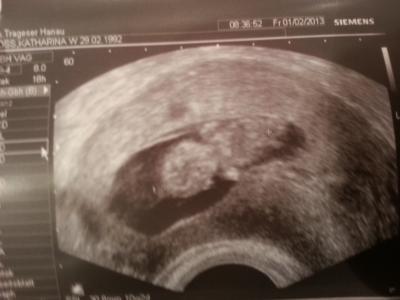

Huhu, War heut morgen beim fa :)) Also is alles ok! Hat genug fruchtwasser, strampelt ganz fleißig und kratzt sich am kopf :) Sah total knuffig aus *-* Lg Ina

Bild zu FA Termin Bericht! - Forum für August - Mamis